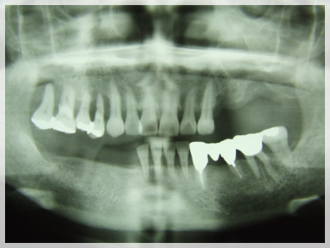

インプラント治療 症例のご紹介1 N様

こちらは当院にて行いましたインプラント治療例の症例写真・パノラマです。

左に1本インプラントを埋入した例となります。

| 治療前 | 治療後 |